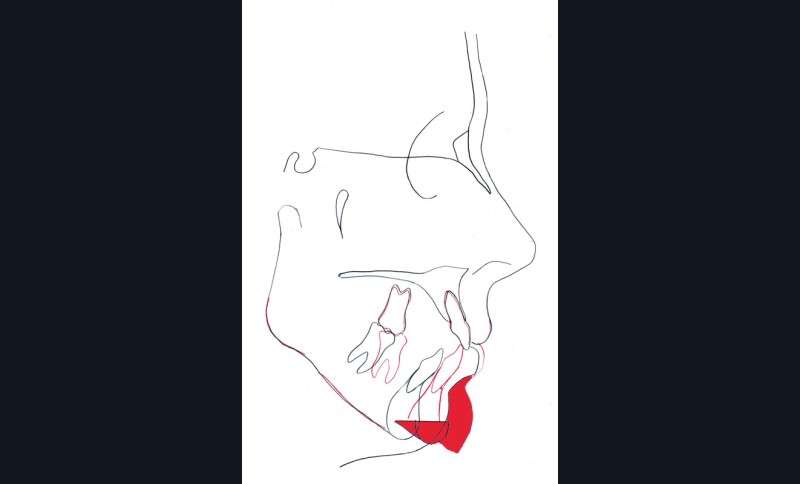

Étapes de traitement

(fig. 2, 3, 4, 5 et 6)

Le plan de traitement retenu a été le suivant :

– disjonction maxillaire assistée chirurgicalement

– préparation orthodontique avec recul molaire mandibulaire sur miniplaques à l’aide de corticotomies alvéolaires

– chirurgie d’avancée mandibulaire et génioplastie soustractive verticale

– finitions orthodontiques et éducation fonctionnelle active labio-linguale

– contentions collées maxillaire et mandibulaire

– suivi, en particulier de la fonction linguale